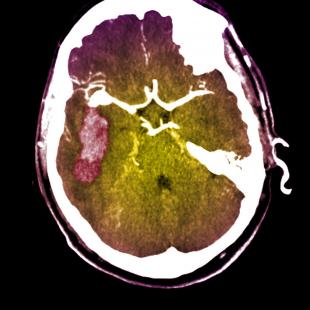

« IL N’EXISTE AUCUN traitement médical qui favorise la réparation et la récupération neurale après un accident vasculaire cérébral », explique au « Quotidien » le Dr Thomas Carmichael (université de Los Angeles) qui a dirigé ce travail. « Or des études d’imageries cérébrales humaines ont montré que la région adjacente à l’AVC se réorganise dans ses connexions et ses aires de mouvement, de langage et de sensations ; et ce processus de réorganisation cérébrale adjacent à l’AVC est corrélé à la récupération. Notre précédent travail indiquait que le cerveau forme un réseau limité de nouvelles connexions dans les régions adjacentes au site d’AVC, un processus dit de bourgeonnement axonal post-AVC car un neurone doit émettre le bourgeonnement d’un nouvel axone. »

« Une question clé pour faire avancer ce domaine est d’identifier le processus moléculaire qui permet au neurone adulte de former une nouvelle connexion ; en d’autres termes, quel est le transcriptome de régénération d’un neurone cortical adulte ? Pour qu’un neurone adulte forme une nouvelle connexion, il doit entrer dans un état de croissance – élaborer des structures spécialisées comme un cône de croissance, allonger l’axone, et former des interactions synaptiques avec d’autres neurones. Cela veut dire qu’un AVC déclenchera un programme de croissance moléculaire dans les neurones adultes, qui est différent des molécules exprimées par un neurone pour le fonctionnement quotidien. »

« Nous avons découvert que l’AVC déclenche effectivement un programme de croissance molé?culaire unique, et que ce programme diffèreremarquablement avec l’âge. Les neurones bourgeonnant âgés montrent par exemple une plus grande activation des gènes du système immunitaire et, de façon paradoxale, ils activent des molécules qui participent à l’inhibition de la croissance axonale – ils essaiment les graines de leur propre destruction. Cette étude a aussi caractérisé plus amplement plusieurs systèmes moléculaires spécifiques (modification épigénétique de l’ADN par ATRX ; facteur de croissance soluble IGF1 ; et inhibition de croissance axonale par Nogo) durant le bourgeonnement axonal post-AVC. »

« Ces résultats soulignent des points importants pour l’application clinique. Premièrement, l’AVC déclenche un programme de croissance moléculaire dans la première semaine de l’événement, et ce programme décline rapidement des la 3e semaine après l’AVC. Deuxièmement, le programme de croissance, ou le transcriptome de régénération, est très différent selon l’âge. Dans le cerveau âgé, il comprend des gènes qui arrêtent directement la croissance de nouvelles connexions. Troisièmement, cela indique que le tissu cérébral adjacent à l’AVC est une région cérébrale hautement active et plastique, et constitue une cible puissante pour de nouvelles thérapies qui favorisent la réparation et la récupération après l’AVC. »